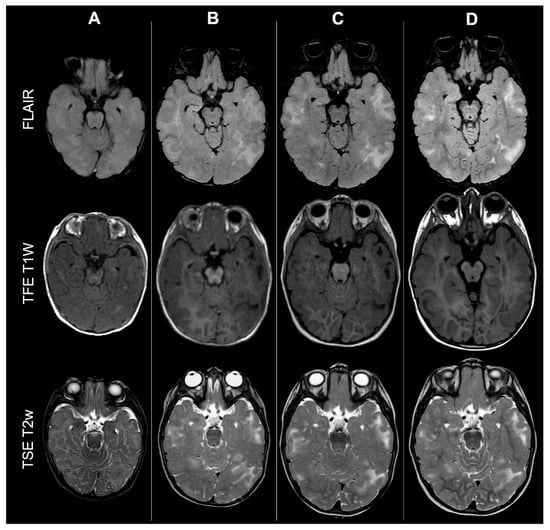

Cortical Tubers’ Transformation in Pediatric Patients Diagnosed with Tuberous Sclerosis Complex: A Retrospective Longitudinal MRI Analysis

Background: Cortical tubers (CTs) are hallmark brain lesions in tuberous sclerosis complex (TSC), historically considered stable in number over time; prior literature has correlated overall CT burden on magnetic resonance imaging (MRI) with disease severity. As longitudinal imaging studies assessing CTs’ evolution over time are lacking, we aim to investigate temporal changes in CTs—both in number and signal—on MRI in a cohort of pediatric TSC patients. Methods: A retrospective single-center analysis was conducted on 57 pediatric TSC patients who underwent longitudinal MRI studies in a 10-year span. Required MRI sequences included volumetric unenhanced T1-weighted, SWI, T2w and/or FLAIR. CTs were evaluated by two neuroradiologists and classified into five subtypes (A, B, C1, C2, D) according to signal characteristics. Statistical comparison was performed using t-tests. Results: Paired t-test analysis demonstrated a significant longitudinal increase in the overall number of CTs, rising from 16.11 ± 12.43 at baseline to 18.77 ± 13.29 at follow-up (mean difference = −2.67, 95% CI [−3.94, −1.39]; t (56) = 4.19; p < 0.0001), corresponding to a moderate effect size (Cohen’s d ≈ 0.56). When stratified by age, patients <2 years—representing the incompletely myelinated subgroup—showed a more pronounced increase in CT burden, from 19.46 ± 15.21 to 24.17 ± 15.75 (mean difference = −4.71, 95% CI [−7.37, −2.04]; t (23) = 3.65; p = 0.0013; d ≈ 0.75). In contrast, patients aged ≥2 years demonstrated a smaller but still significant increase, from 13.67 ± 9.45 to 14.85 ± 9.64 (mean difference = −1.18, 95% CI [−2.08, −0.28]; t (32) = 2.68; p = 0.0115; d ≈ 0.46). Direct comparison between the two subgroups using Welch’s two-sample t-test confirmed that the mean CT count in patients <2 years was significantly higher than in those ≥2 years (mean difference = 3.53 ± 1.36; t = 2.59; df = 28.4; p = 0.0075), with a large effect size (Cohen’s d ≈ 0.78). Type C1-C2 tubers evolved from pre-existing earlier-stage lesions, while most newly visible CTs over time were type A-B. Type D tubers remained rare and derived from earlier-stage CTs. Conclusions: Contrary to previous assumptions, CTs in pediatric TSC showed a tendency to increase in number and evolve in signal over time, thus challenging the notion of stability and suggesting dynamic behavior. Incomplete myelination in early infancy may impact MRI CTs detection by reducing contrast with surrounding brain tissue, potentially leading to their underestimation/misidentification. Full article

Show Figures

Figure 1